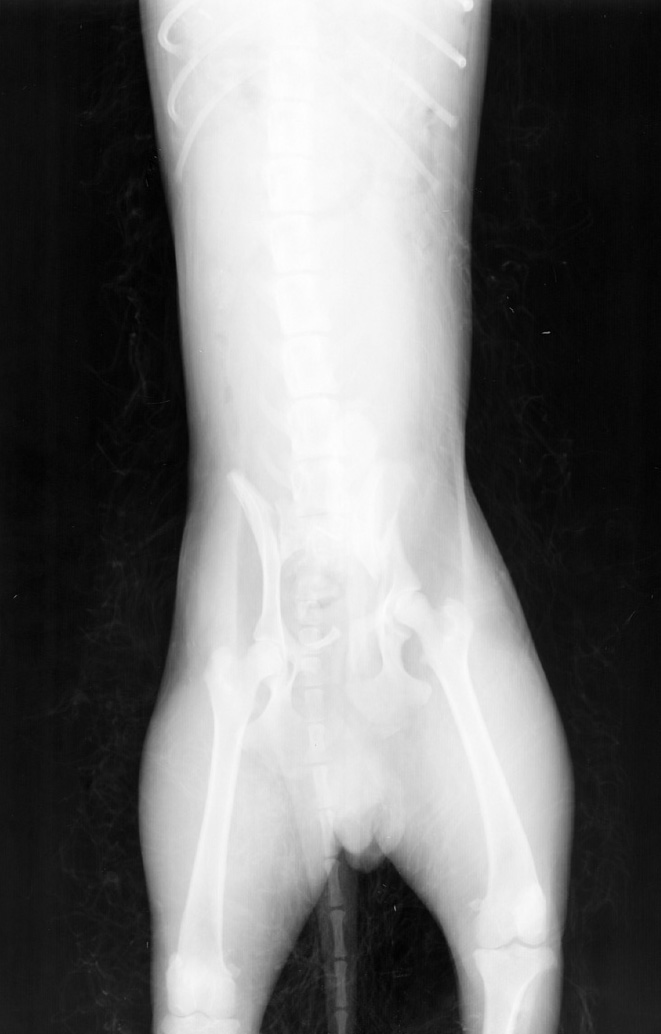

Wet Hair Coat

White linear artifact seen over the dog's abdomen due to prescence of wet hair coat.